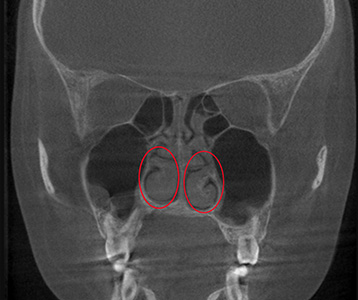

• 재수술 전

• 재수술 후